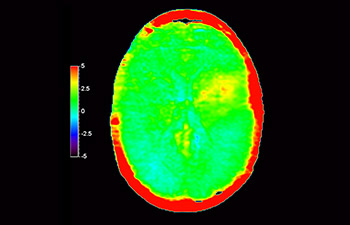

Brain lesion

with 3D APT